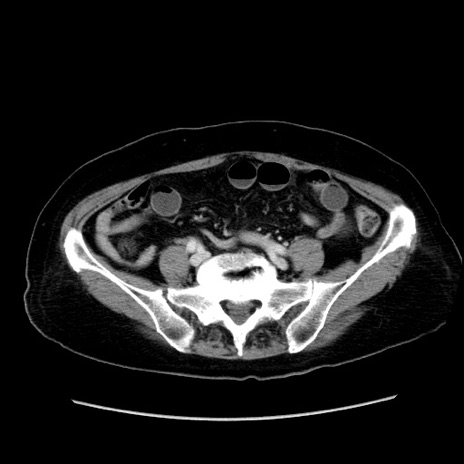

症例19(横断像)

【症例】80歳代女性

【主訴】下腹部痛

【現病歴】約8時間前より下腹部痛の出現あり、救急外来受診。

【既往歴】両側付属器切除

【身体所見】意識清明、下腹部正中に手術痕あり、その部位に一致して圧痛と反跳痛あり。腸蠕動音は亢進。

【データ】WBC 9300、CRP 0.15